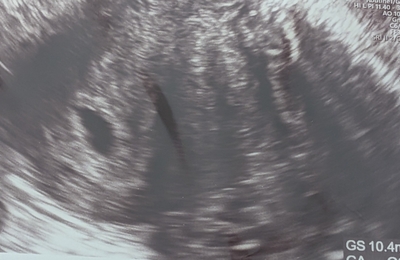

今日は妊娠7週3日目。2回目の心拍確認のため、不妊治療クリニックへ行ってきました。診察では、赤ちゃんの胎芽の大きさが 10mm にまで育っていて、しっかりと心拍も確認できました。小さな命がちゃんと育ってくれていることに、胸がいっぱいです。そして先生からは、「次の検診で問題がなければ、卒業ですね」との言葉が…!ついに、次回の診察で 不妊治療クリニックを卒業予定 となりました🌸通い始めてから1年半。採…

🍁11/29 6w0d 11/5 → 凍結胚移植🥚 11/13 → 陽性判定🧚 こんにちは( ^ω^ )☀️ 今日から6週だぁ〜🥰 眠い&胸の張りがあり、 つわりはなし! 夕方から疲れたりくらいかなぁ。 息子の育児しながらだから めーっちゃ何かを感じたりは ないので逆に不安・・・w 前回はもうこの時期につわりが 始まってたような・・・😭 でもぶっちゃけないならないでいい👍w ということで先週土曜日…